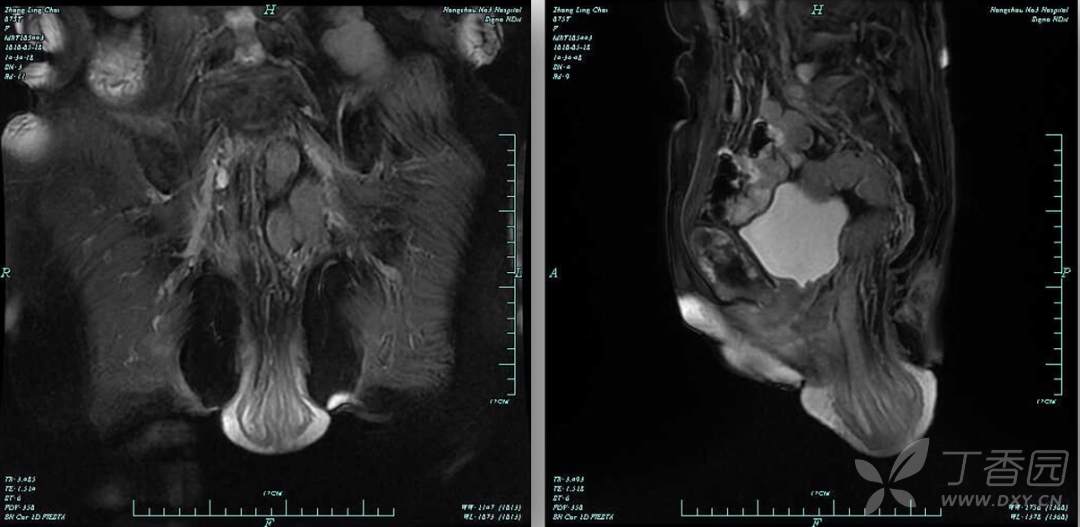

盆腔 MRI:直肠全层脱垂。肠镜:直肠粘膜松弛,直肠粘膜炎症。